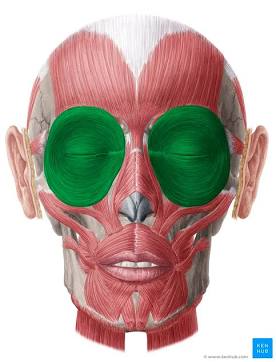

Orbicularis

Circular.